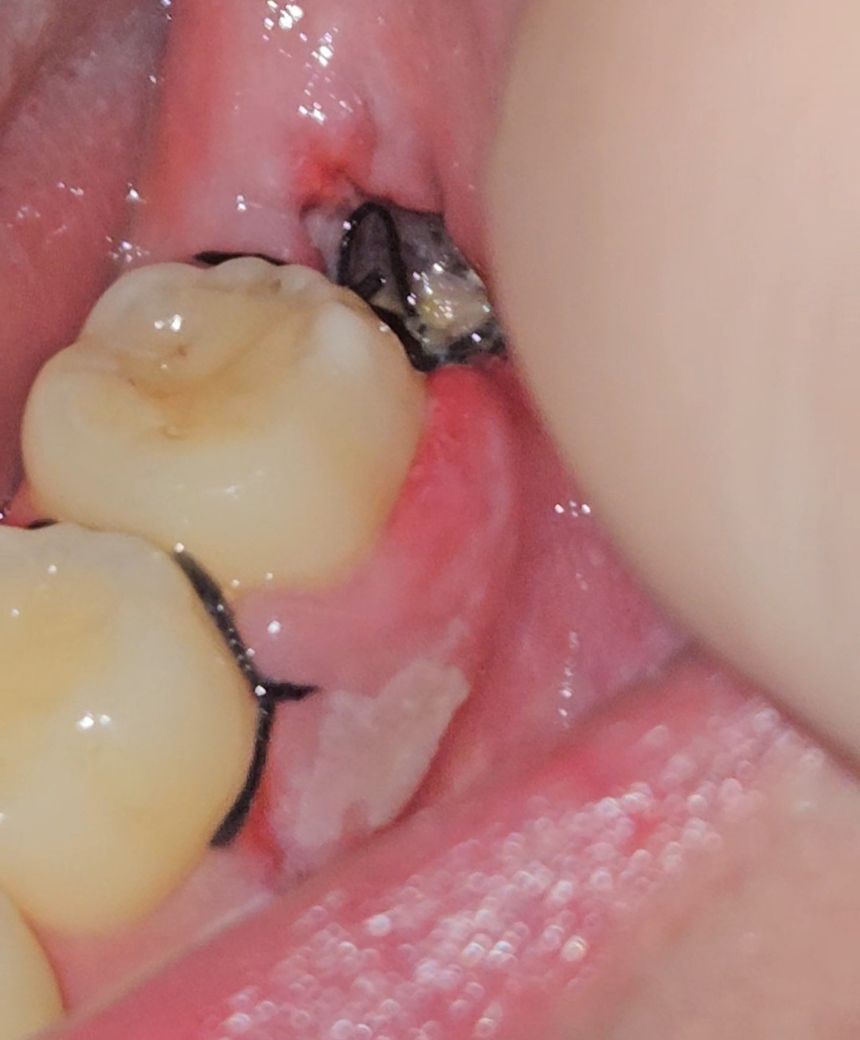

사랑니 뺀 자리에 이거 드라이소켓인가요?

사랑니 발치 후 6일차입니다

방금 보니 혈병이 없고 뼈가 보이는거 같습니다

지금은 발치 자리에 통증이 딱히 없는데

이거 드라이소켓인가요?

6일차라면 현재와 같이 보일 수 있으며 이는 드라이소켓이 아닙니다. 드라이소켓은 엄청난 통증이 동반되게 됩니다. 또한 혈병은 초기에 나타나게 되며 시간이 지나면 섬유화 과정을 거쳐 사라지게 됩니다. 현재 사진으로 보아서는 크게 걱정하지 않으셔도 됩니다.

안녕하세요 치과의사 김철진입니다. 드라이 소켓은 감염의 일종으로 통증이 심하고 냄새도 심하게 납니다. 사진상으로 보면 드라이 소켓은 아닌거 같습니다.

사진으로는 정확한 상태를 확인하기 힘들어 보입니다. 드라이 소켓이 있는 경우에 극심한 통증이 생기기 때문에 통증이 없다면 드라이 소켓이 아닐 가능성이 높습니다. 자세한 확인을 위해서 치과에서 진료를 받아오는 것을 전해드립니다.

사진상으로 혈병으로 보이지는 않으며 현재 정상으로 아물고 있는것으로 보입니다. 해당부위에 염증이 덧나지 않도록 헥사메딘가글액으로 가글하여관리하여주길 권합니다.

드라이소켓이라면 발치 후 3~5일이 지났을 때에 참기 어려울 정도의 옆으로 퍼지는 듯한 통증이 느껴집니다. 통증이 딱히 없다면 걱정안하셔도 됩니다.

드라이소켓으로는 보이지 않습니다. 드라이소켓의 가장 큰 특징은 통증이 극심하고 악취가 많이 나는 것이기 때문에 해당 증상과는 거리가 있습니다.

6일차면 이제 혈병은 없고 그 자리를 새로운 잇몸 상피 세포가 채우기 위해 열심히 재생이 일어나고 있는 것입니다.

흰색 막 양상이 무조건 드라이소켓은 아닙니다. 육아조직 등 세포 재생 시 발생하는 다양한 물질도 그런 양상을 띌 수 있습니다.

특별히 통증이 없고, 발치 후 주의사항을 잘 지켰다면 걱정하지 않으셔도 됩니다.